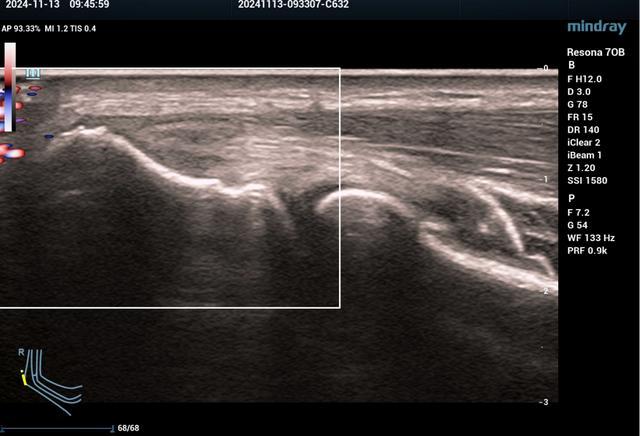

3、腕关节超声检查

腕管综合征、桡骨茎突狭窄性腱鞘炎(妈妈手)、扳机指、类风湿性关节炎、拇长屈肌腱断裂、前臂交叉综合征等。

▲前臂近端交叉综合征

▲指屈肌腱腱鞘炎

(扳机指)